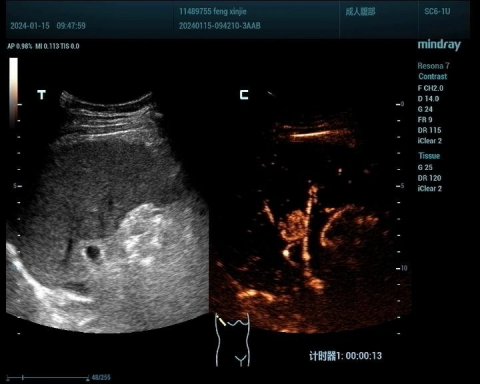

肝癌病例1